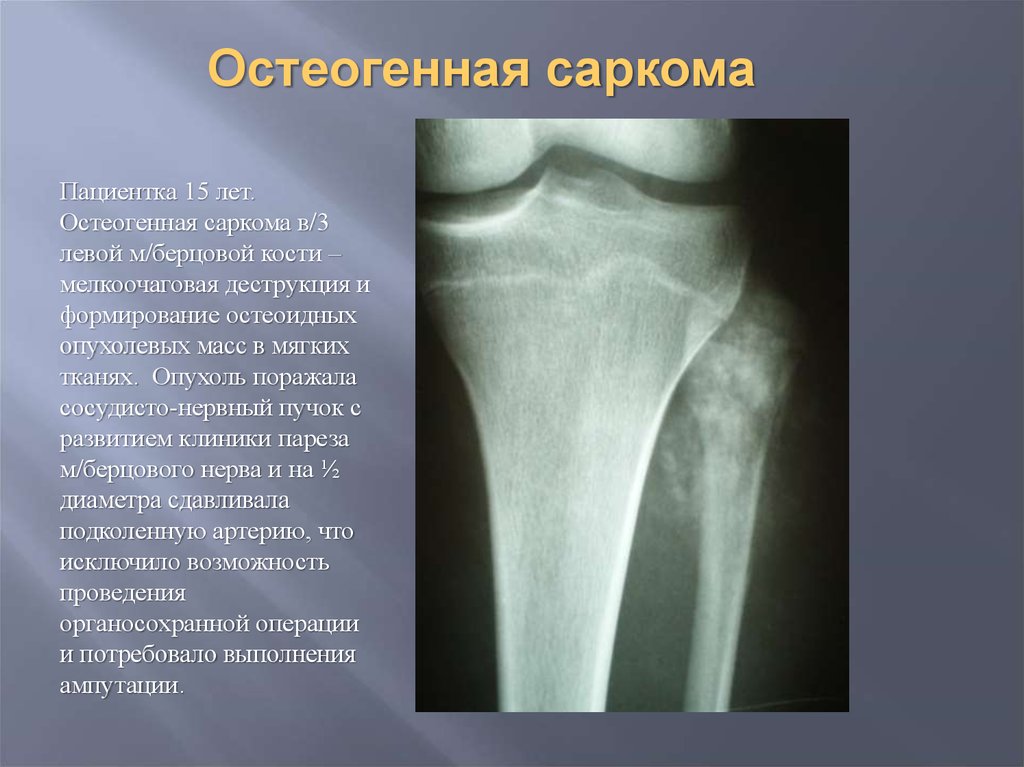

Остеосаркома коленного сустава: информация и поддержка

Раздел: Необычные решения